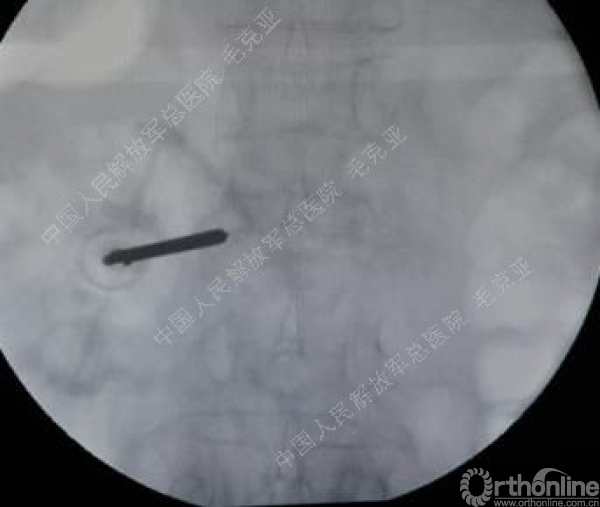

毛克亚:新型弯角椎体增强装置的研制与临床应用研究

导语:随着社会老龄化的不断加速,骨质疏松性椎体压缩骨折作为一种普遍存在的老年骨科疾病已经成为现今骨科界的一个热点话题。传统的保守疗法治疗效果不佳,而现有的椎体增强技术又具有多种风险和缺陷。针对这种现状,中国人民解放军总医院毛克亚教授提供了一种新的解决方法。